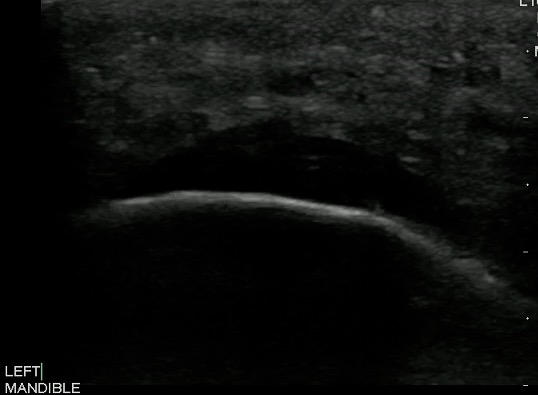

- Figure 5 and 6. Normal Mandible

- Bony structures like mandible, maxilla appear hyperechoic with a posterior hypoechoic acoustic shadow underneath.

- Fat has hyperechoic appearance on ultrasound.

- Muscles are generally visualized as hypoechoic structures but have a more heterogeneous striated appearance.

- Normal Mandible:

Video 4. Normal Mandible